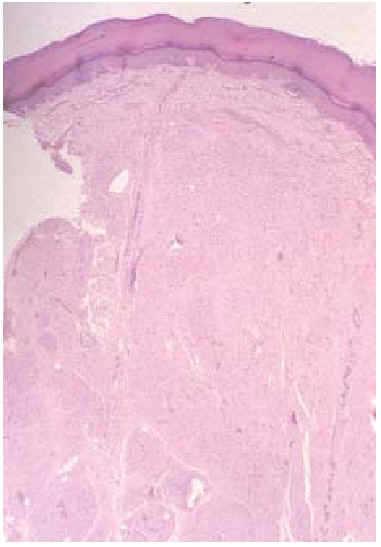

En el estudio histológico de la tumoración de la palma de la mano se observó una proliferación de células fusiformes de pequeño tamaño que ocupaban la dermis de forma difusa. En profundidad se agrupaban con un patrón plexiforme bien definido, intercalándose focalmente entre los adipocitos (fig. 3). En áreas se agrupaban formando estructuras que imitaban a corpúsculos de Meissner (fig. 4). Con la técnica para la proteína S100 se teñían tanto las células fusiformes como los corpúsculos tipo Meissner. Con ello se llegó al diagnóstico histológico de neurofibroma con un patrón difuso en dermis y plexiforme a nivel subcutáneo.

Fig. 3.--Infiltración dérmica de células fusiformes. En profundidad las células se agrupan con un patrón plexiforme. (Hematoxilina-eosina, x20.)